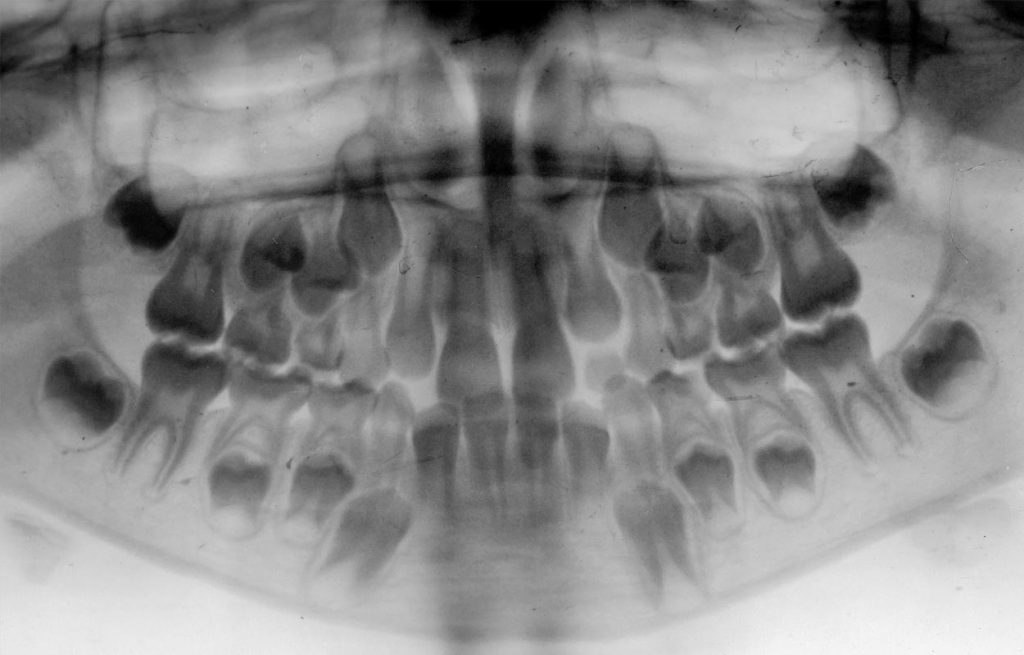

Suaugusiųjų dantų priežiūros įgūdžiai formuojami nuo ankstyvos vaikystės – su tuo ir susieta suaugusiųjų dantų būklė. Todėl į gendančius vaikų dantis – tiek pieninius, tiek nuolatinius – negalima „numoti ranka“. Nuo vaikų pieninių dantų būklės tiesiogiai priklauso ir nuolatinių dantų užuomazgų vieta ir būklė, ir kaip taisyklingai ar ne tie nuolatiniai dantys išdygs.

Besiformuojančios nuolatinių dantų užuomazgos po pieniniais dantimis

Vaikų pieninius dantis būtina išsaugoti sveikus arba nors laiku suplombuotus, kol nuolatinių dantų užuomazgų keliami, pieniniai dantys atsipalaiduos natūraliai, ir vaikų odontologas padės juos pašalinti. Nuolatinių dantų užuomazgų vystymuisi bei taisyklingam dantų dygimui nepalanku, jeigu sugedę pieniniai dantys negydomi ir pašalinami per anksti arba per vėlai.